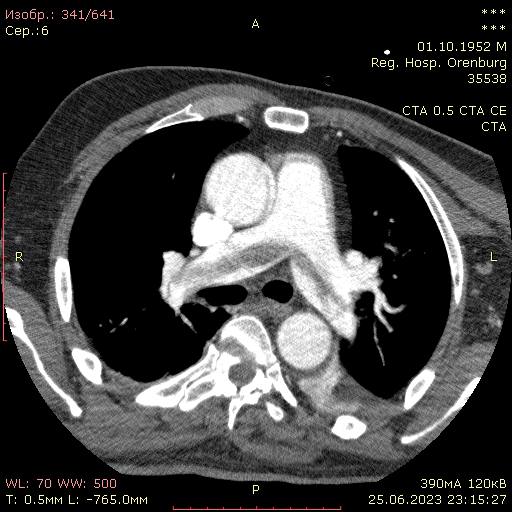

В медучреждении проходил лечение 70-летний пациент у которого течение основного заболевания осложнилось массивной тромбоэмболией легочной артерии. КТ-ангиопульмонография выявила, что тромб больших размеров, располагается в легочном стволе с переходом в обе легочные артерии.

После операции состояние пациента улучшилось. У мужчины уменьшилась одышка, повысилась сатурация кислорода. Через 5 дней после процедуры контрольная КТ-ангиопульмонографии показала, что легочный ствол и легочные артерии свободны от тромбов, единичные фрагменты тромбов есть в мелких ветвях легочных артерий, что свидетельствует об эффективности проведенного вмешательства.